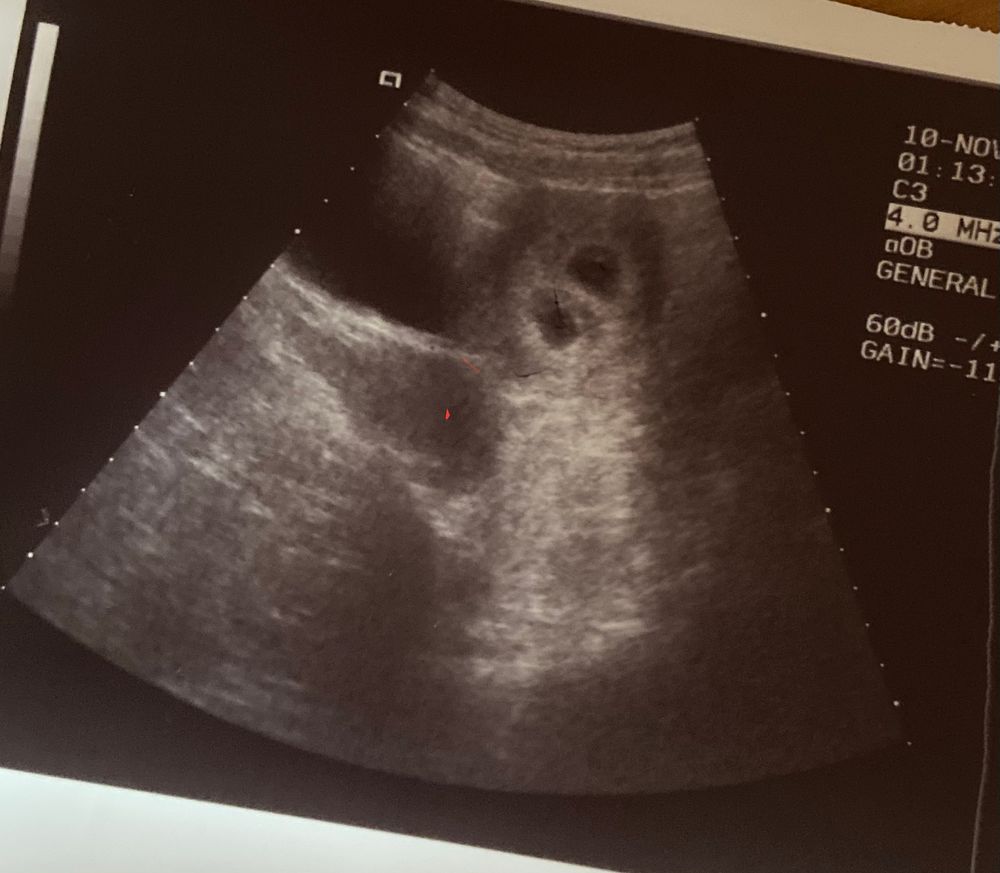

28 дпп,узи,эмбрион и жм очень очень слабо визуализируется.

Добрый вечер. Сегодня было первое узи. 28дпп. Есть два плодных яйца, 21мм, по словам врача эмбрионы и жм слабо видны, в заключении написал что не визуал вообще, сб-сказал что в одном из них есть пульсация, в заключении написал что сб нет. Я читаю девочек , у очень многих на этом сроке уже все видно. Девочки, напишите пожалуйста что думаете по этому поводу, или как у кого было. Я что то переживаю …